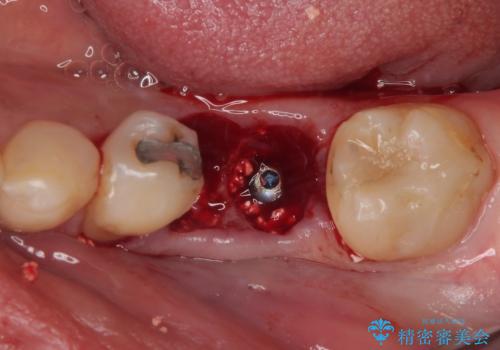

下顎大臼歯の抜歯即時埋入インプラント治療では、複数ある歯根のうち、後方の歯根部にインプラントを埋入することで一般的であり、今回破折して骨吸収が著しいのは前方の歯根であったため、事前に仮歯を用意した上で、抜歯即時埋入インプラントによる補綴治療を行うこととしました。

来院されるまではインプラント治療を躊躇されていましたが、抜歯即時埋入により、単回の外科処置で治療が終えられることのメリットを理解され、インプラントによる補綴治療を行いました。

スムーズに治療を終えることができました。